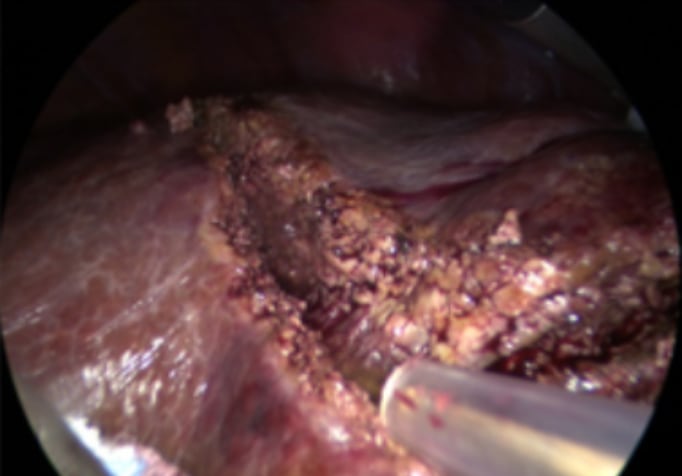

Nonanatomical resection for colorectal liver metastasis in segment 8. Without mobilizing the right hemiliver a good view is obtained.

Nonanatomical resection using CUSA

Picture showing large tear in right hepatic vein. The patient was positioned in semiprone. CVP during parenchymal transection was 8. Although CVP was relatively high, blood loss was minimal giving the surgeon time to suture the venous tear.